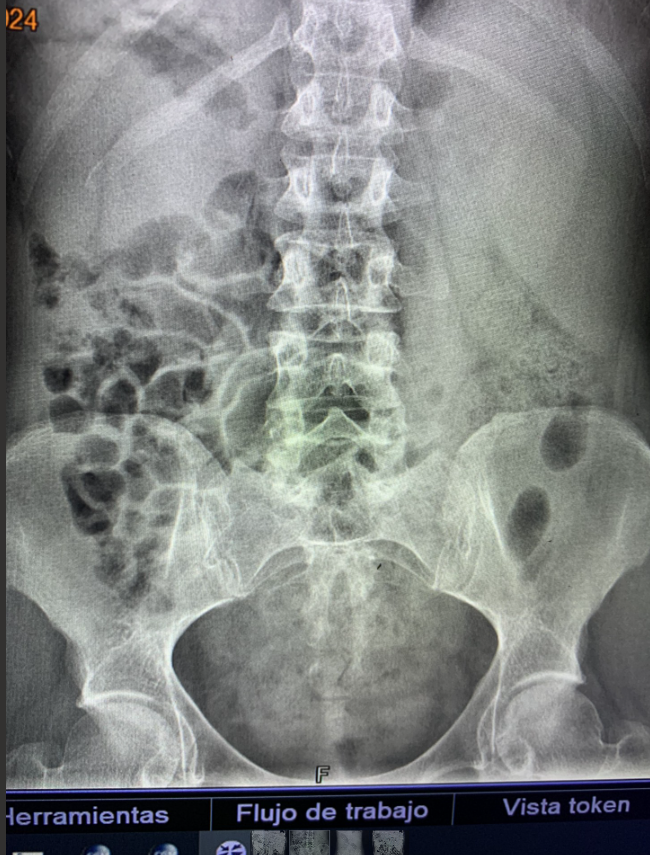

Radiografía Abdomen: Asas de delgado en marco colónico derecho. Gas en marco colónico izquierdo, Heces en ampolla rectal, sin niveles hidroaéreos (no describen anormalidades).

Identificación de problemas: No teníamos el antecedente de situs inverso, en su historia clínica previa, no hubo una interpretación correcta de la radiografía abdominal previa.